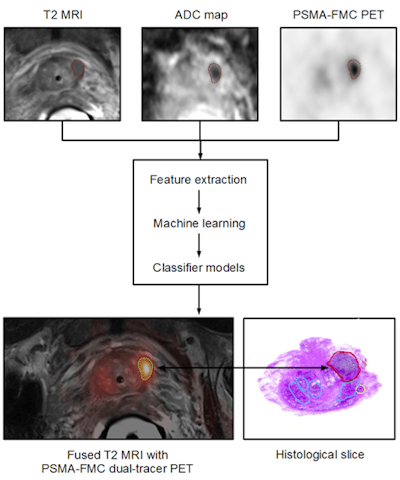

Figure 5: A conjoined assessment and understanding of tumor biology and molecular pathology enables the definition and validation of novel biomarkers for both diagnostic and therapeutic options, including therapy-response assessment. Figure courtesy of Ludwig Boltzmann Institute, lb:l, Vienna, Austria.Moreover, the sum of this information, including quantitative and imaging biomarkers, genetic predispositions and phenotypes, can help develop computer-assisted prediction models that will provide clinicians with a priori information on lesion classification (figure 6) and, possibly, predictive therapy response. It is with this sensible combination of recent technical and methodological advances that we need to look beyond simple imaging and move away from a "me > you" perspective to a collaborative and innovation-centric perspective on how to best assess disease and help patients most effectively.

Figure 6: Patient with prostate cancer undergoing dual-tracer PET/MRI and subsequent ex vivo histopathology of the prostate. Combined PET/MRI includes T2-weighted MRI for anatomical referencing, Diffusion weighted imaging (DWI) for estimating cellular density and sequential Ga-68 PSMA and F-18 FCH imaging. Multiparametric image data processing supports the extraction of specific image features that are entered into a machine-learning (ML) process and subsequent computer-supported classifiers, which, based on sufficient and validated training efforts, permit the delineation and classification of tumor heterogeneity. Image courtesy of Laszlo Papp and Dr. Markus Hartenbach, Medical University Vienna, Austria.If you would like to learn more about this approach to applied diagnostics, or become part of it, you may want to attend the next cross-specialty symposium, "Applied Diagnostics for Effective Cancer Treatment" (www.applied-diagnostics.eu) in Vienna in late September. There, you will find a forum of experts from both academia and industry in the field of molecular pathology, nuclear medicine, clinical pharmacology, and beyond who share this vision and like to engage in advancing effective and individualized treatments based on novel and validated diagnostic approaches.